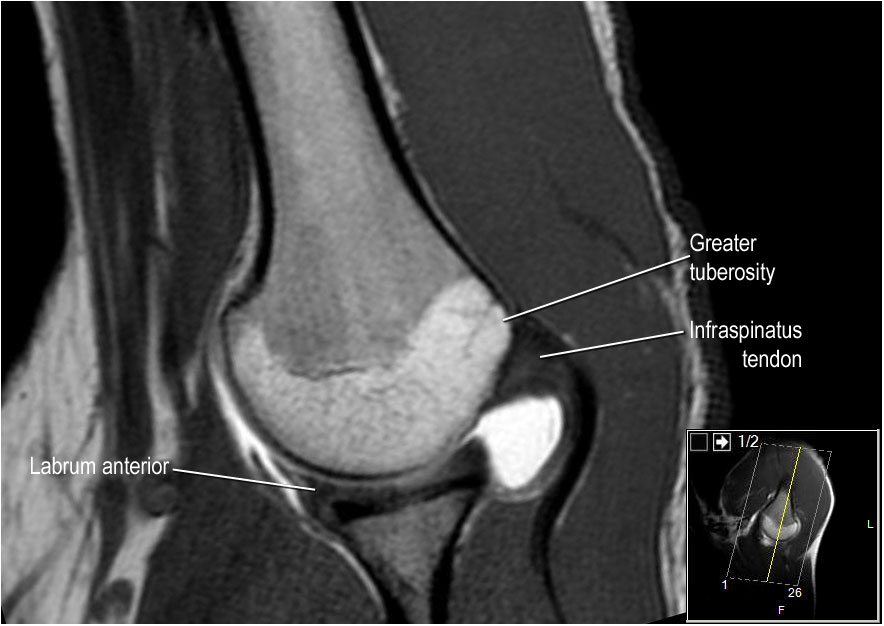

Hình ảnh mặt sau

Hình ảnh thể hiện các cơ và gân của cơ trên gai, cơ dưới gai và cơ tròn bé. Tất cả đều bám vào mấu động lớn.

Các cơ và gân chóp xoay có chức năng ổn định khớp vai trong quá trình vận động.